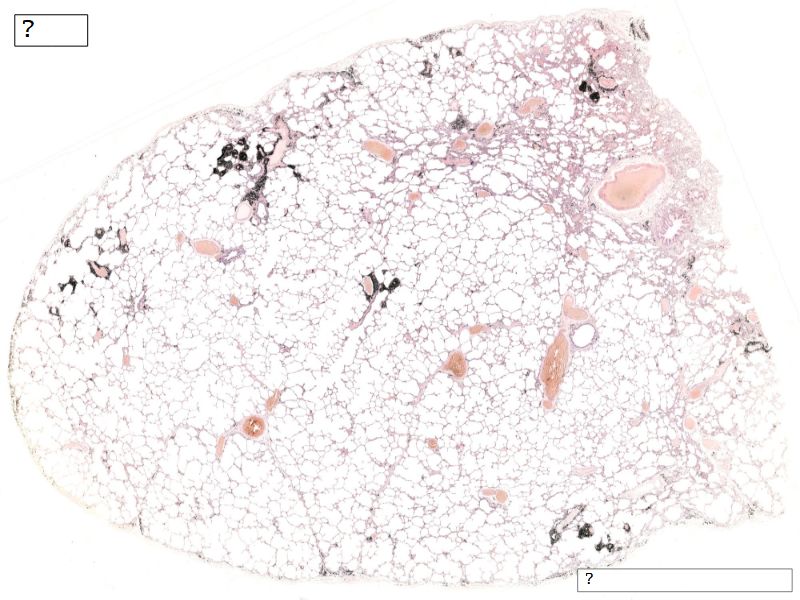

Fill in all the missing labels, and assess as you move through the slides. Answers on the down slide. It is important to do this using pen and paper, and not just glance through the images.